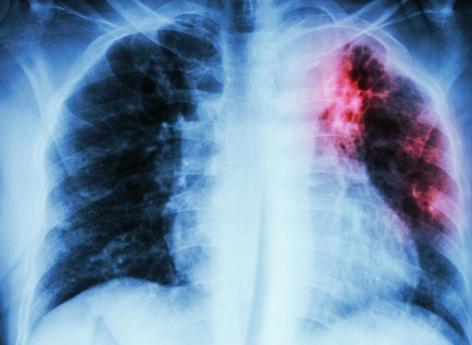

La tuberculose est due à une bactérie (Mycobacterium tuberculosis) qui touche le plus souvent les poumons. C’est une maladie que l’on peut prévenir et soigner, indique l’OMS. Elle se transmet d’une personne à l’autre par voie aérienne : "Quand une personne ayant une tuberculose pulmonaire tousse, éternue ou crache, elle projette des bacilles tuberculeux dans l’air. Il suffit d’en inhaler seulement quelques-uns pour s’infecter".

Les radiographies du thorax de 498 patients ont été analysées rétrospectivement. Cinquante-sept (11 %) de ces patients avaient reçu un diagnostic de tuberculose, dont 41 cliniquement et 16 par des tests PCR (Xpert MTB/Rif). Ce test détecte simultanément le complexe Mycobacterium tuberculosis (MTBC) et la résistance à la rifampicine (RIF), spécifiques de la tuberculose, en moins de 2 heures.

D’après l'expérience, le logiciel d'IA a correctement identifié 75 % de tous les cas confirmés par PCR et 85,7 % des cas non tuberculeux. Le radiologue moins expérimenté a lui correctement identifié 62,5 % des cas confirmés par PCR et correctement identifié 91,7 % des cas non tuberculeux. Les évaluations du radiologue expérimenté étaient eux de 75 % pour les cas confirmés par PCR et de 82 % pour les cas non tuberculeux.